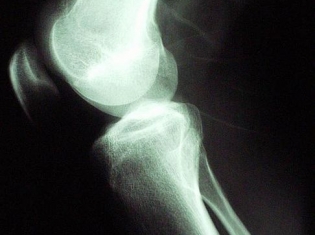

Activities like running, which has a high impact on the knees, was linked with greater wear on the cartilage, researchers found. This higher risk also increased the odds of developing osteoarthritis.

Using magnetic resonance imaging, researchers took photographs of patients' knees at the start of the study and after two and four years. They specifically looked at cartilage in the kneecap and the major bones of the lower right leg. The participants tracked how often they exercised and were physically active.